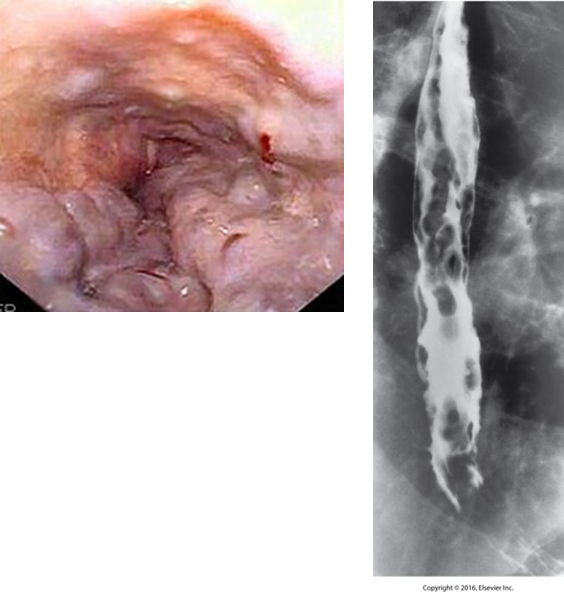

Esophageal Varices

Dilated veins in the distal esophagus.

Caused by portal hypertension.

May bleed.

Radiological Appearance

Wavy border, thickening folds

Appear as round or oval filling defects (beads